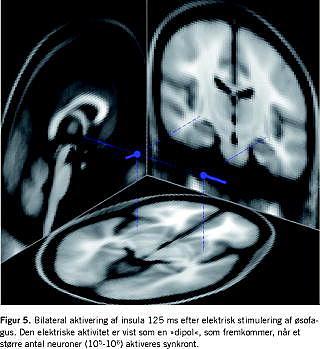

Man kan måle det sensoriske respons med validerede skalaer, men da f.eks. smerte er et overordnet begreb, som indeholder information om tid, sted, kvalitet og styrke - foruden affektive og kognitive komponenter - er disse skalaer udtryk for den subjektive opfattelse af et meget komplekst fænomen. Hvis den successive aktivering af de forskellige dele af det perifere og centrale nervesystem skal forstås mere detaljeret, må man anvende metoder, som giver en detaljeret information om nervesystemet. For at opnå denne information kan man bruge billeddiagnostiske og neurofysiologiske metoder. Metoder, der er baseret på billeddiagnostik, er begrænsede af, at processeringen af smerter gennem forskellige centre i hjernen foregår inden for få millisekunder. Hvis man skal opnå en forståelse for, hvilke centre der er aktive i den ascenderende aktivering af neuroaksen, må man derfor måle den neuronale aktivitet direkte. De fleste steder anvendes elektroencefalografi (EEG) eller magnetencefalografi. Sammenlignet med magnetencefalografi er EEG-signalet fra de neuronale strukturer forvrænget af bl.a. hud og knogle, men det har den fordel, at man kan måle den dybe hjerneaktivitet, og udstyret er billigere. De tekniske problemer kan i stor udstrækning løses med signalanalytiske metoder. Den moderne computerteknik har gjort analyse af store datamængder mulig og har bidraget til at løse »det inverse problem« - dvs. at beregne hjernenaktiviteten baseret på den elektriske aktivitet målt i hovedbunden. Typisk kombinerer man sin matematiske model med en MR-skanning af personens hjerne, så individuelle forskelle i anatomi ikke begrænser beregningerne. Der findes forskellige modeller til at løse det inverse problem, men det har for nylig vist sig, at hvis man opløser signalet i individuelle bølgeformer, kan man beregne lokalisationen af det aktive center i hjernen med en nøjagtighed på få millimeter - og i realtid - Figur 5 [9]. Man har bl.a. anvendt sådanne metoder til at sandsynliggøre, at smerterne ved kronisk pancreatitis er af neurogen oprindelse [10]. Det er også vist, at hjernens bearbejdning af smerter hos patienter med funktionelle tarmsygdomme som f.eks. colon irritabile minder om dem, man kan fremkalde hos raske, når øsofagus sensibiliseres med syre. Disse ændringer kan måske forklare den allodyni, der er et kendetegn ved mange af disse patienter, og som kan manifestere sig ved smerter ved normal afføring og luft i tarmen.